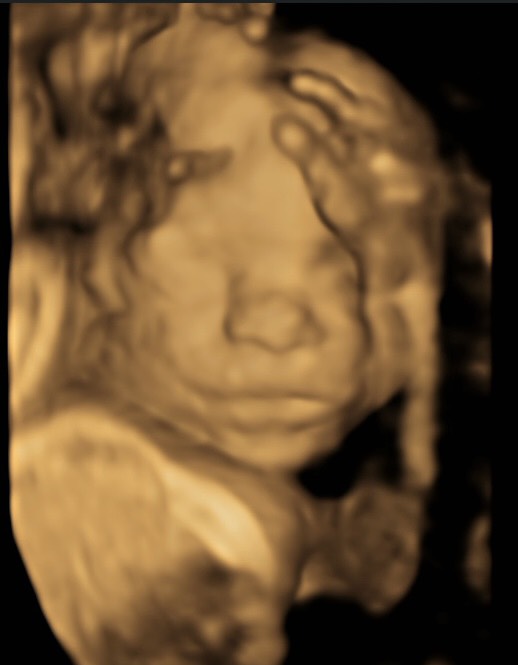

Арсений передает привет, закрывался руками, потом повернулся спиной: что это значит?

post image 2

Арсений передает привет, закрывался руками, по итогу повернулся спиной 😅